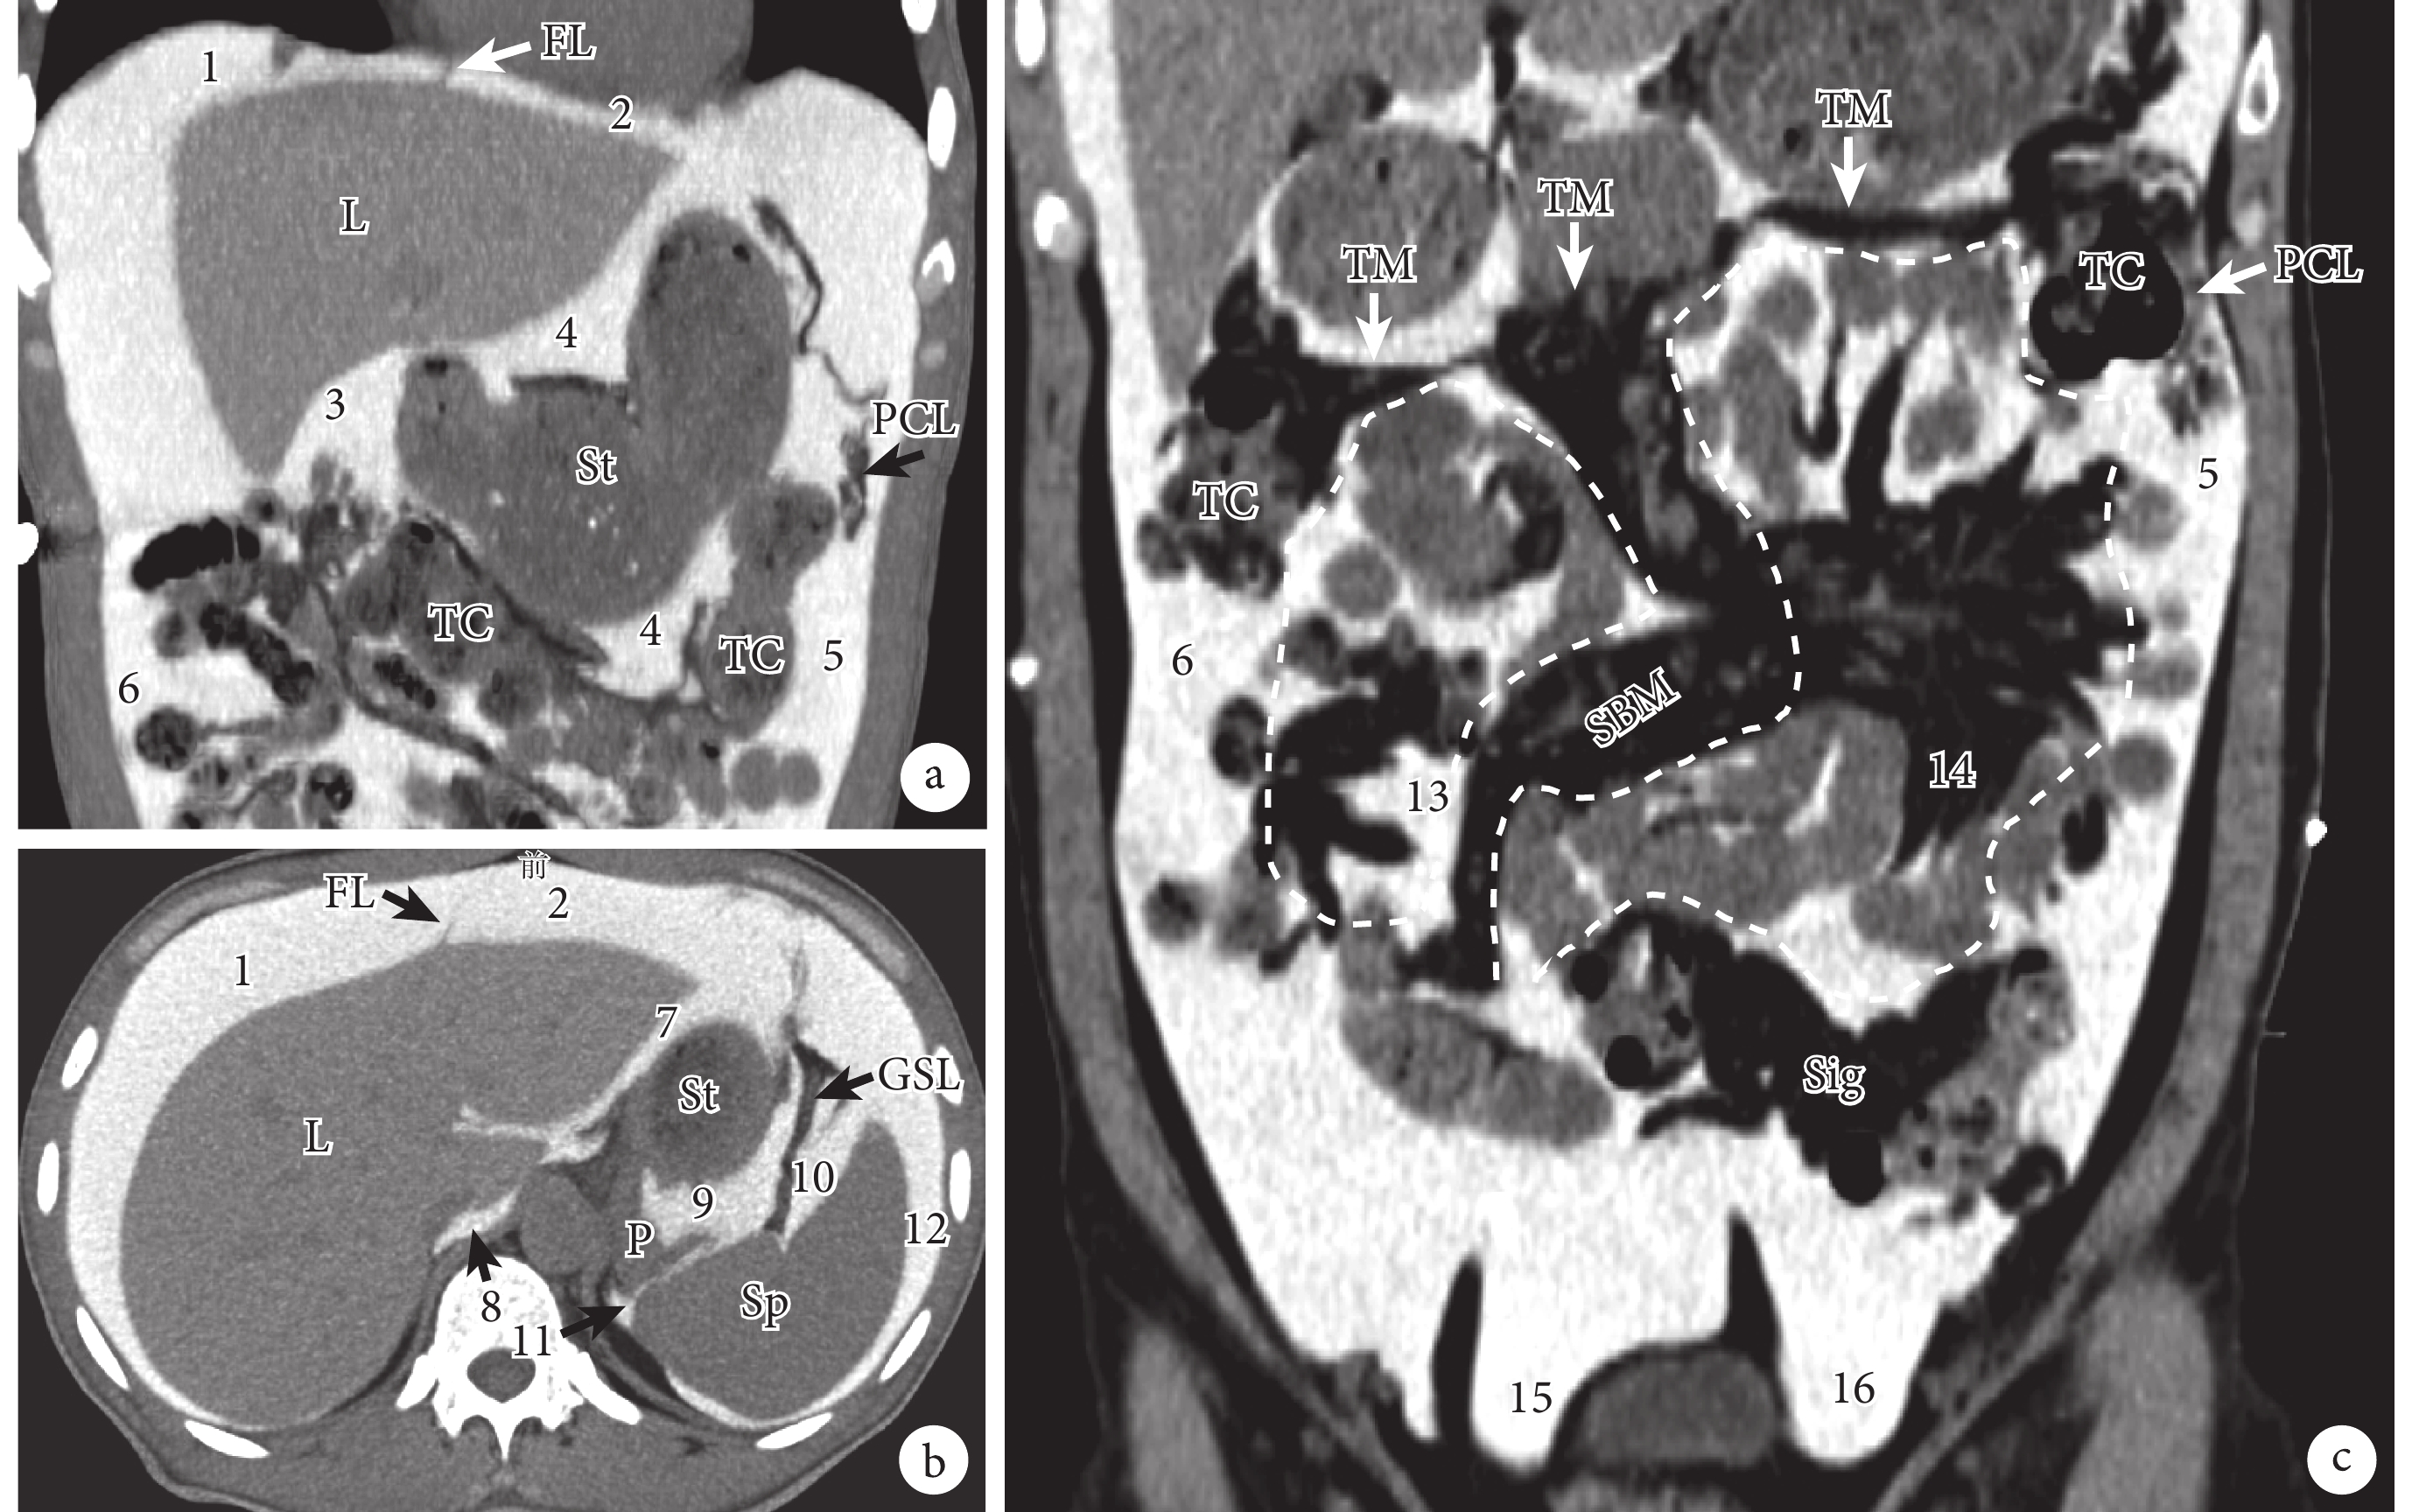

a、b:結腸上區的主要腹膜腔間隙;c:結腸下區的主要腹膜腔間隙。1:右肝上間隙;2:左肝上間隙;3:右肝下間隙;4:網膜囊;5:左結腸旁溝;6:右結腸旁溝;7:左肝下間隙;8:網膜囊上隱窩;9:網膜囊脾隱窩;10:胃脾隱窩;11:脾腎隱窩;12:脾外側間隙(脾周圍隱窩);13:右結腸下間隙;14:左結腸下間隙;15:右直腸旁窩;16:左直腸旁窩;FL:鐮狀韌帶;L:肝臟;St:胃;PCL:膈結腸韌帶;TC:橫結腸;GSL:胃脾韌帶;P:胰腺;Sp:脾臟;TM:橫結腸系膜;SBM:小腸系膜;Sig:乙狀結腸

結腸上區位于橫膈和橫結腸及橫結腸系膜之間,以肝鐮狀韌帶為界又被分為右結腸上區和左結腸上區(圖2a、2b)。結腸上區的解剖較為復雜,并且對于結腸上區各腹膜腔間隙的命名也并未達成完全一致[2-3, 5-6]。